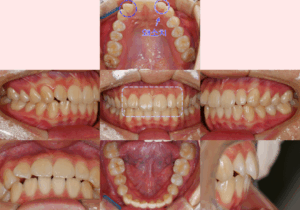

면목동 치과 틀어진 앞니(나비 치아)가 고민인 20대 환자, 상악골 확장 marpe 활용해 비발치 교정으로 도와드린 사례

안녕하세요^^ 글로리 김정은 대표 원장입니다. ​ 오늘은 많은 환자들께서 고민하고 계시는 부분인 "틀어진 앞니"에 대한 내용을 다뤄볼 예정인데요. ​ 저희 면목동 치과 에서는 어떠한 방법을 활용해 개선을 도와드렸는지에 대해 설명드리고…